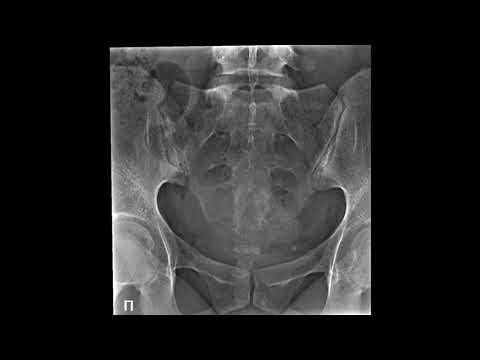

Укладка пальцев стопы